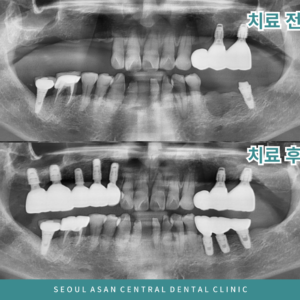

단대오거리치과, 전체 임플란트로 건강한 삶을 회복시켜 드리는

단대오거리치과, 전체 임플란트로 건강한 삶을 회복시켜 드리는 심한 충치나 파절, 외상으로 인한 손상이 아니더라도 치아를 발치하게 되는 경우가 있는데요. 바로 치주 질환에 의한 발치입니다. 치주 질환은 우리나라 성인 인구의 70%…